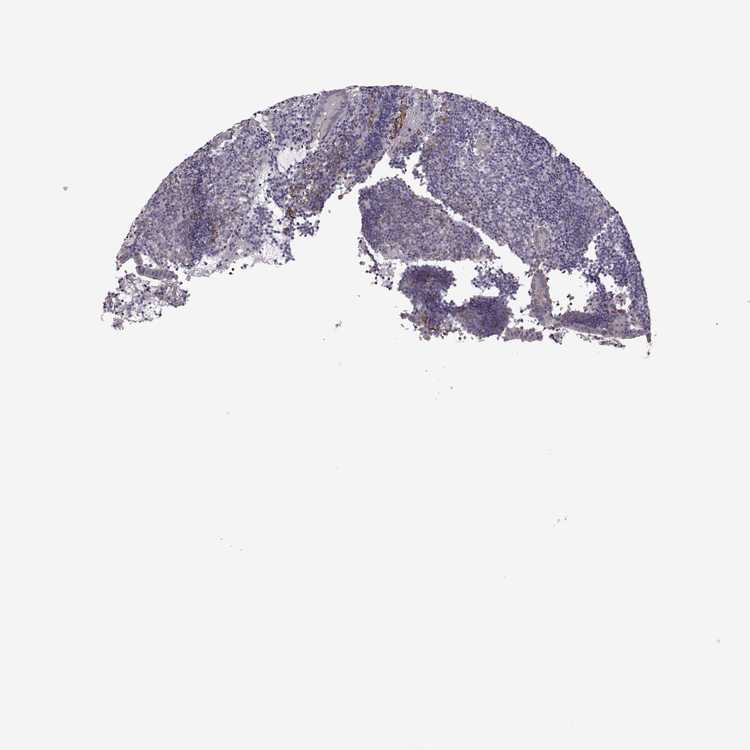

APPENDIX - Antibody stainingi

Antibody staining in the annotated cell types in the current human tissue is reported as not detected, low, medium, or high, based on conventional immunohistochemistry profiling in selected tissues. This score is based on the combination of the staining intensity and fraction of stained cells. Each image is clickable and will lead to virtual microscopy that enables deeper exploration of all samples and also displays staining intensity scores, fraction scores and subcellular localization as well as patient and tissue information for each sample.

Antibody HPA030665Antibody HPA068563Antibody CAB037231

Glandular cells Not detectedNot detectedMedium

Lymphoid tissue Not detectedNot detectedNot detected